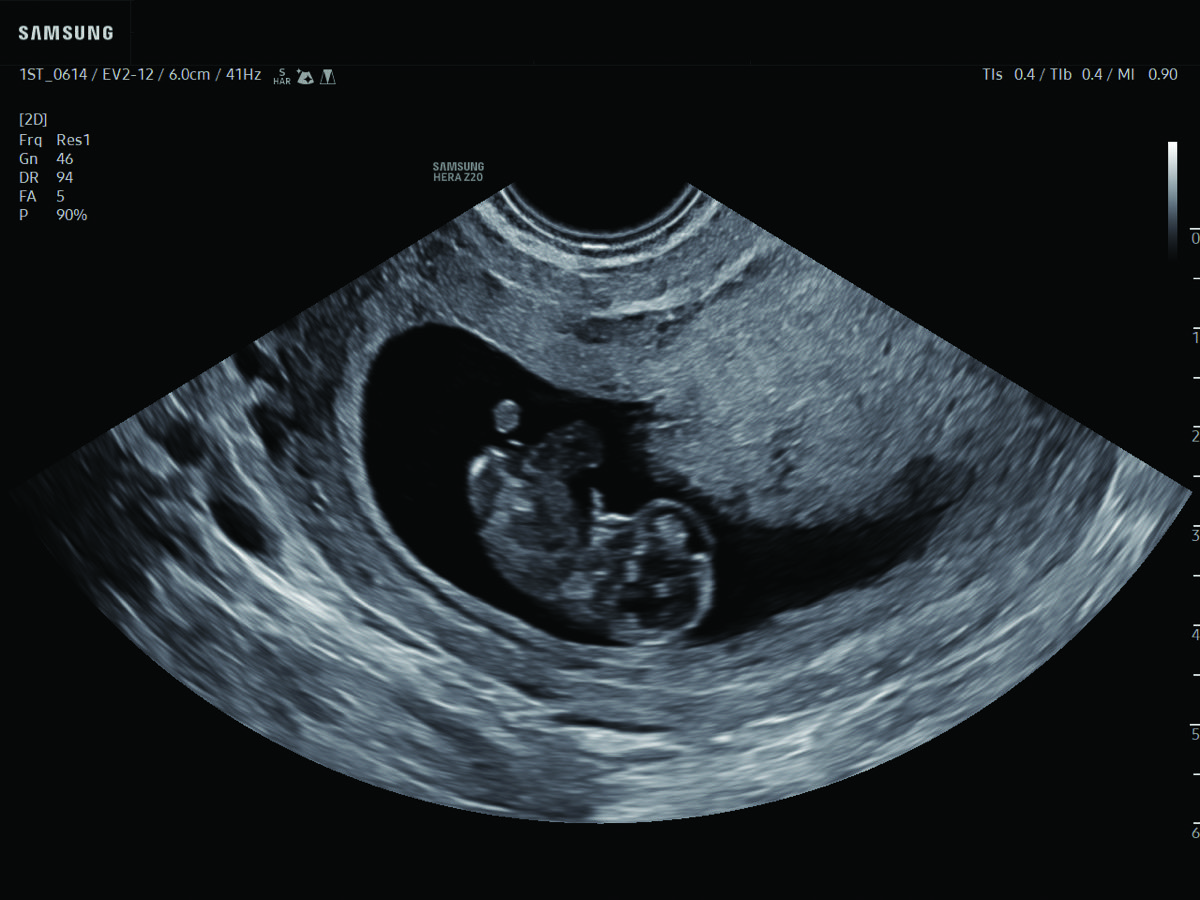

In-depth evaluation of maternal and fetal conditions requiring specialized care such as diabetes, hypertension, thyroid disease, autoimmune disorders, or fetal growth or anatomy concerns.

Comprehensive, advanced and expert MFM care for high-risk pregnancies